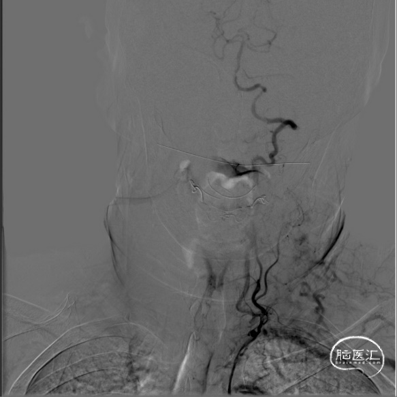

术前DSA影像:

右侧桡动脉穿刺置动脉鞘,泥鳅导丝配合6F 115cm Valent®颅内支撑导管内嵌行至右侧锁骨下动脉近右侧椎动脉起始段处,将导丝配合中间导管上行至椎动脉V3段,撤出泥鳅导丝,手推造影,显示:基底动脉中段可见重度狭窄,狭窄率约80%。